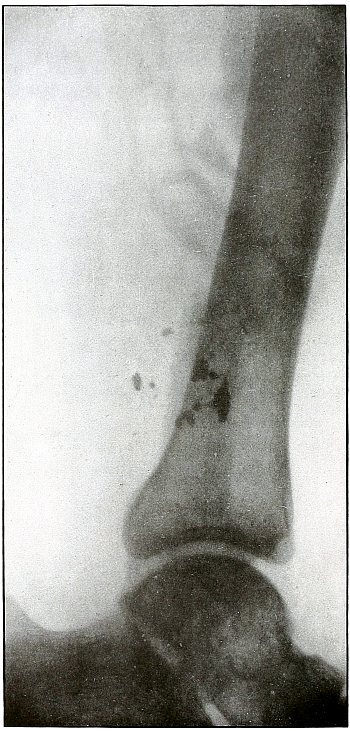

Rifle—Plate 55.

LOWER EXTREMITY.

Gunshot Fracture of the Lower Third of the Shaft of the Femur.

The course of the bullet was diagonally anteroposterior, with a velocity near mid range, without causing much displacement of fragments.

The wound of entrance and exit would be almost the same in appearance.

Treatment and results would be similar to case shown on plate 54. Many of these wounds are infected, due, no doubt, to the difficulties of arranging a clean first-aid dressing and effecting satisfactory immobilization during the first stage of transportation.

Infection from clothing carried into the wound is rare, as the fairly high velocity of the bullet causes a spreading of the fibers without division or punched-out section before the bullet.

As a rule the infected cases of this class recovered without loss of limb. Amputation was very rare. [Pg 122]